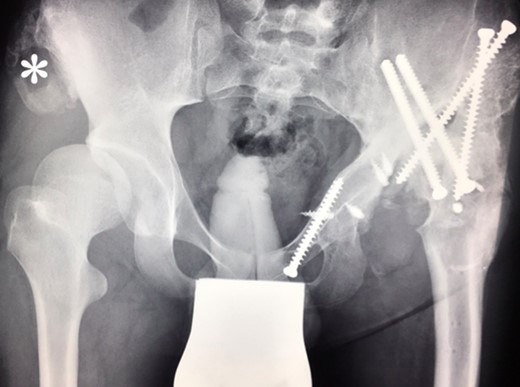

Ten years ago, a 12-year-old male presented to our clinic complaining about limping and massive swelling of the left hip. Figure 1 shows the initial X-ray and the 3D reconstruction of the left hip at first presentation when the femoral head, had already destroyed the lateral edge of the acetabulum like a mortar. Severe pain episodes have apparently not been noticed and a former hip dysplasia was not known. A brief clinical history revealed that the patient presented repeated episodes of finger biting and fevers from 2 to 8 years old. The intelligence level of the patient was at an average. The patient was admitted to a paediatric neurologist and a genetic test. A mutation of the NTRK1 gene was found and the diagnosis of CIPA was established. The right hip initially appeared to be normal and the patient was walking, therefore surgical reconstruction for the left hip was proposed due to massive swelling, inability of normal walking and significant limb length discrepancy. A Tönnis/Kalchschmidt triple pelvic osteotomy with open reduction and a shortening varus derotation osteotomy (VDRO) of the femur was performed (Fig. 2A–B). After 3 months the patient was walking again but another 3 months later the hip dislocated again without severe pain. Although the femoral head was already damaged the hip joint was reconstructed again by open reduction, capsular reconstruction with suture anchors and a trevira tube and a movable external fixator was used to temporary stabilize the joint (Fig. 3). The right hip at this time was still intact and was protected with a pneumatic orthotic device. A few months later in 2009, despite all surgeries, the left hip had entirely lost congruency and the right hip developed subluxation despite conservative treatment (Fig. 4). The patient was still walking so the decision to reconstruct the right hip with open reduction, capsular augmentation with a trevira tube, a triple pelvic osteotomy and VDRO was made (Fig. 5). Few months later this reconstruction failed as well and the hip dislocated without severe pain (Fig. 6).

(A + B): (2008) (A) Hip reconstruction with open reduction, Tönnis triple pelvic osteotomy and shortening rotational varus osteotomy of the left femur demonstrating correct deep reposition in ap view. (B) Lauenstein view shows that the acetabular congruency over the femoral head is restored.